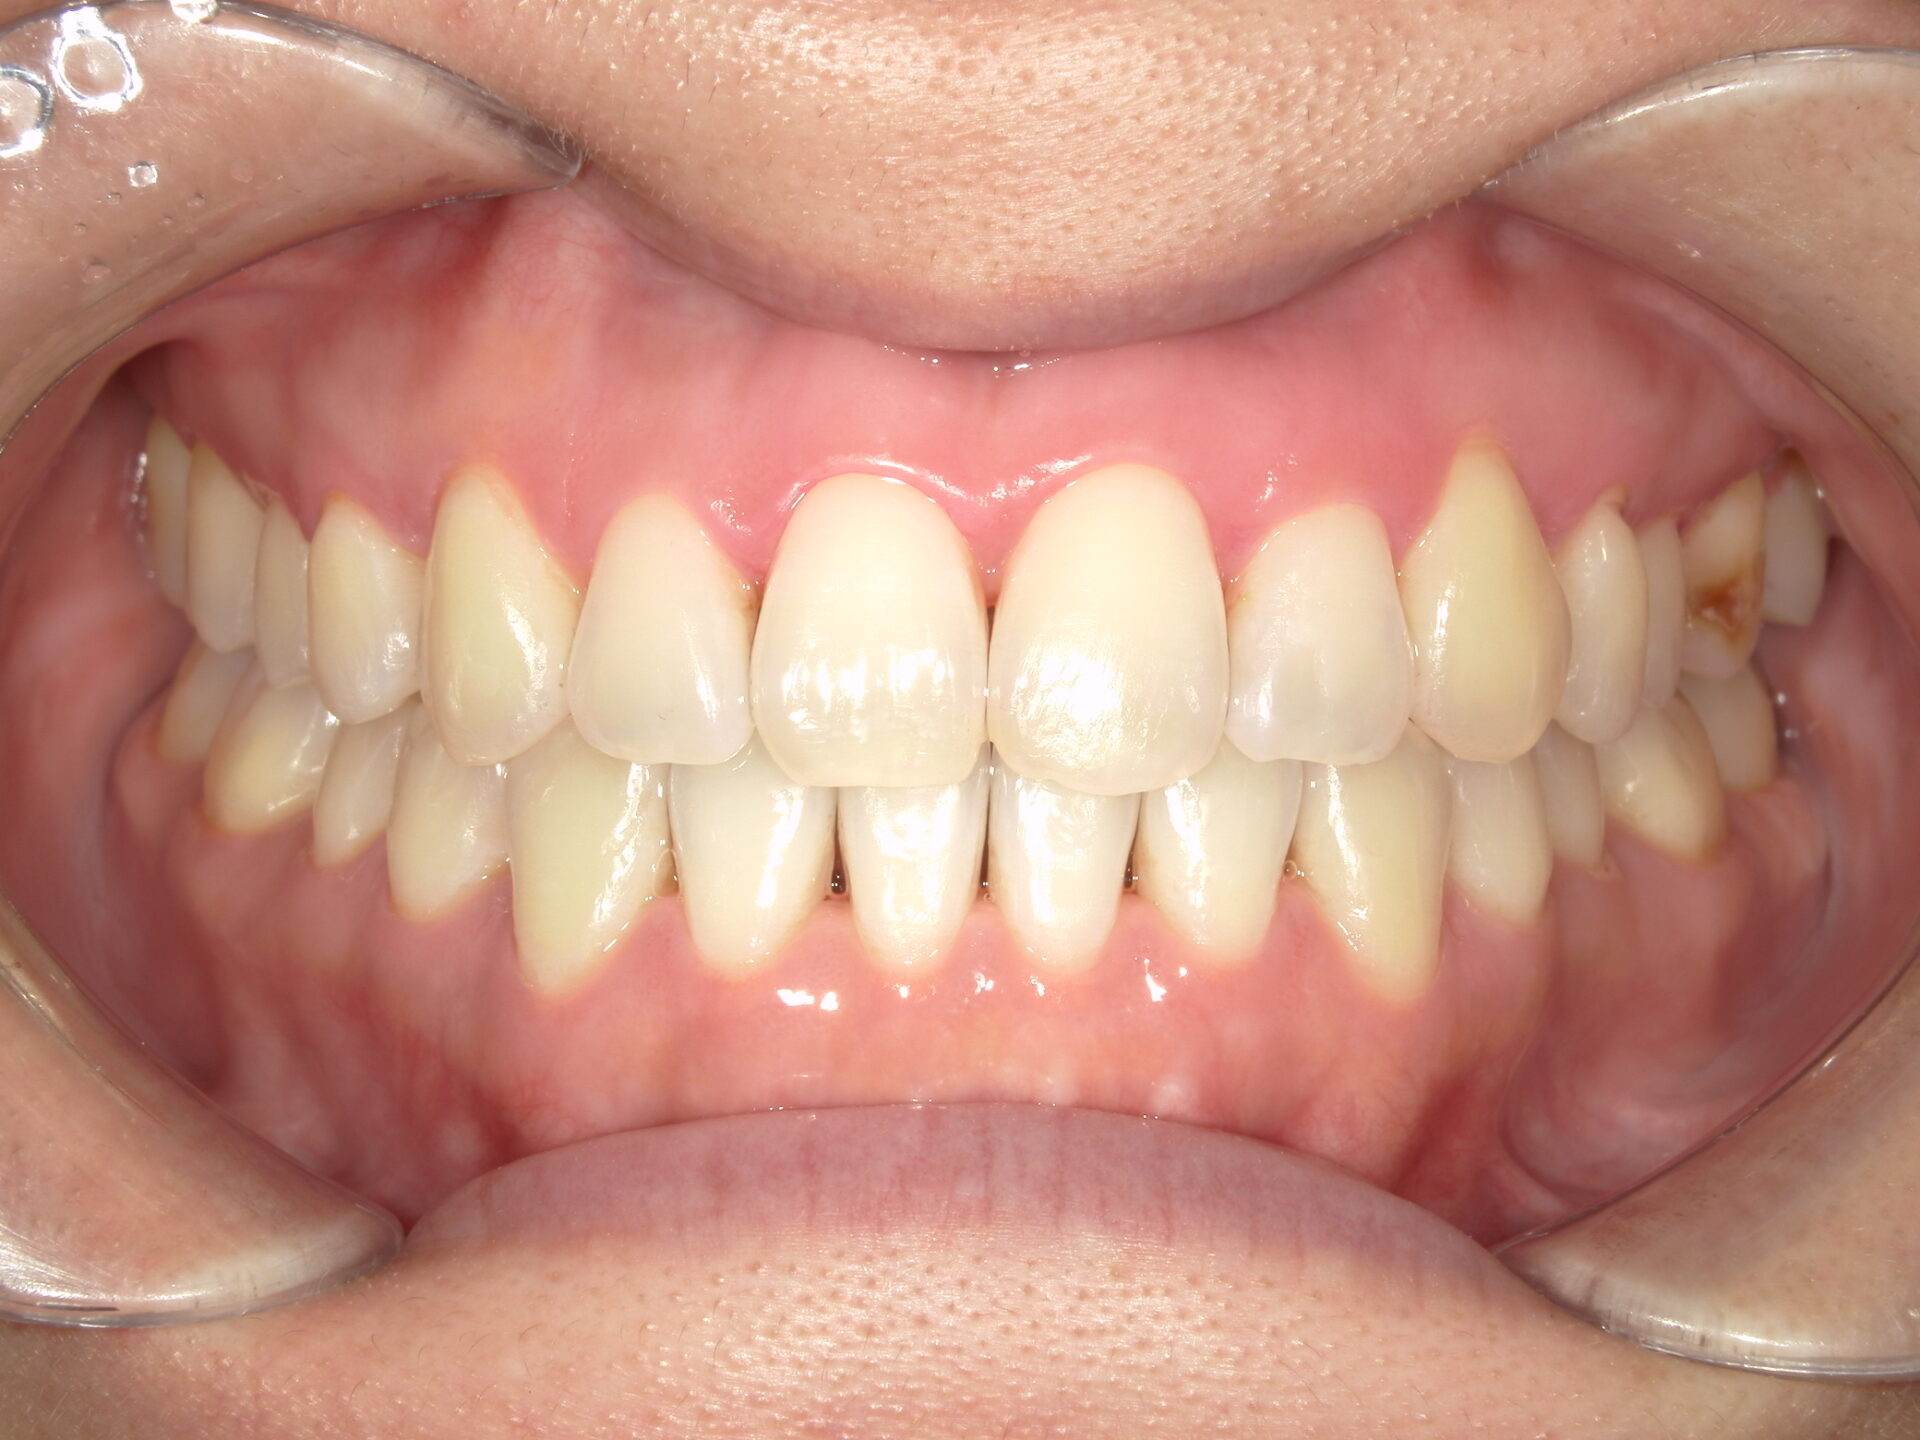

after

患者さんの年齢 20代 女性 症状 ガタガタを治したい 治療内容 マウスピース矯正治療 費用 90万(税抜) 治療期間・回数 治療期間2年、通院回数10回 メリット 笑顔が綺麗 デメリット・リスク 期間がかかることがある - マウスピース矯正